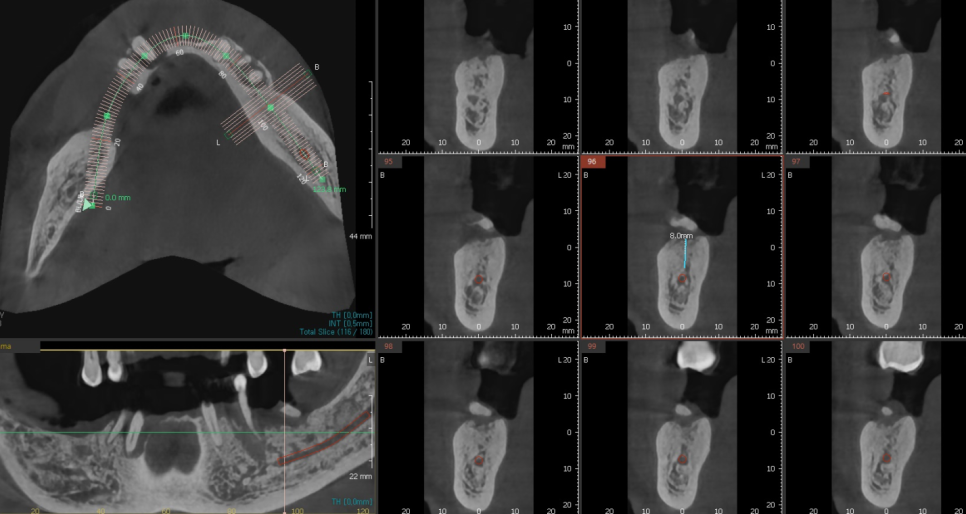

ct등을 통하여 임플란트 수술 계획이 결정되는데요.

임플란트는 뼈에 식립하기 때문에

골밀도와 잇몸 상태를 고려해 수술 방식을 결정해야합니다.

이에 따라 임플란트 재료도 달라질 수 있고

필요 시에 따라 잇몸치료나 뼈 이식이 진행될 수도 있습니다.

사실상 진단만으로도 임플란트 식립 사이즈 , 개수 등이

결정된답니다.

오늘 환자분도 골밀도를 분석하여

남아있는 뼈의 양을 측정

임플란트 사이즈까지 적어 왜 뼈이식이 필요한지

설명드렸었거든요~~

저희 병원은 디지털 방식으로

네비게이션 임플란트를 사용하여 정교하게 진행하고 있는데요.

이 방법은 수술 시간이 짧고 통증을 최소화할 수 있어 환자들의 만족도가 높습니다.